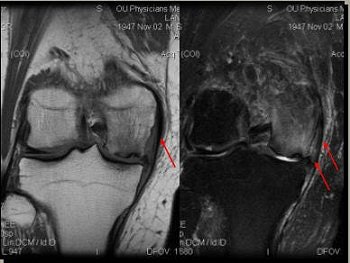

![]() |

| Edema in MCL from osteochondritis dissecans (OCD) and chrondomalacia. |